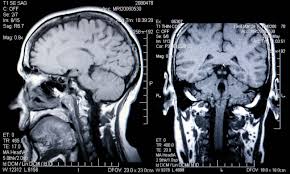

MRI Sample Images

Brain MRI scans showing different stages of Alzheimer's progression.